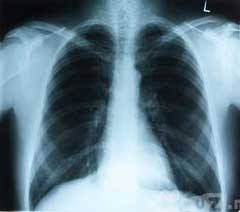

Konsideran penting dari larangan merokok di Belanda, yang dituangkan dalam Tabakswet (UU Tembakau) adalah tegas: demi melindungi rakyat dari penyakit jantung dan pembuluh darah, kanker, dan puluhan jenis penyakit kronis lainnya seperti COPD atau chronic obstructive pulmonary disease (penyakit paru kronis obstruktif).

Baik merokok aktif maupun merokok pasif itu sangat merusak kesehatan, terutama anak-anak dan wanita hamil jika mereka terpapar asap rokok (merokok pasif, alias ikut menghirup asap rokok yang disemburkan oleh orang lain yang merokok).

Pertumbuhan bayi dalam kandungan terbukti terganggu akibat asap rokok, antara lain ditunjukkan dengan berat badan bayi yang ringan saat kelahiran. Sedangkan pada anak-anak, asap rokok dapat menyebabkan gangguan pertumbuhan dan penyakit kronis pada saluran nafas.